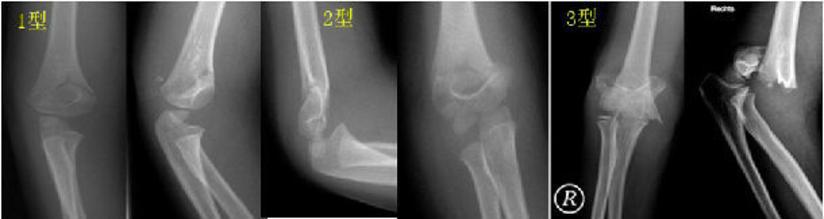

影像基础 肘关节骨折的影像学诊断及分型 移位